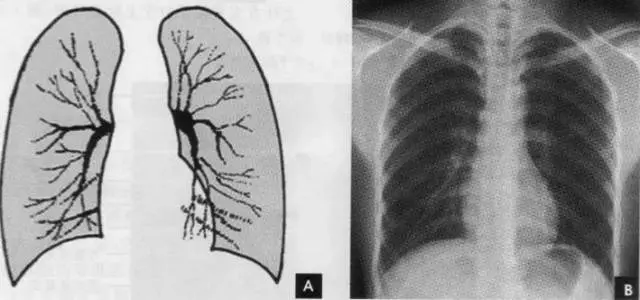

临床拍标准的胸部正位片其实是后前位片,如上图。

上图为正常胸部后前位片

2.肺纹理

肺纹理为自肺门向肺野呈放射状分布的树枝状阴影,它主要是肺动脉的投影,肺静脉、支气管和淋巴管也参与形成。肺纹理由肺门向外围延伸,逐渐变细,至肺野外带渐细小而稀少,距侧胸壁内缘约1cm范围内的肺野基本无肺纹理可见(图下图)。